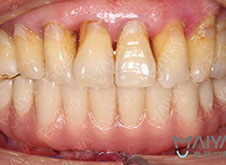

据冯先生介绍,他的全口牙从几年前就开始损坏了,平时会伴随牙疼、牙龈出血等,当时并没有什么明显的剧痛感觉,所以多年来也没有在意。直到几个月前发现缺失牙临近的牙齿有点松动,接着牙齿开始脱落,后来也上网查阅了资料,才发现缺牙不修复危害大:缺牙部位相邻牙齿少了支撑,容易倾斜导致松动,很多人都因为忽视,从而导致相邻牙齿逐渐松动脱落,不仅导致咀嚼功能急速下降,影响了生活质量,而且口腔结构的改变直接影响面容,会让人看起来比实际年纪苍老,冯先生不禁为缺牙烦恼起来。

日常饮食经常塞牙 缺失牙临近的牙齿松动脱落 咀嚼功能急速下降 生活质量大打折扣 影响面容易显苍老 更多隐患

麦芽口腔专业医生提醒:牙齿缺失是一种常见口腔疾病,虽然很多人对牙齿保健有了足够的认识,但依然有许多人认为,缺一两颗牙无所谓,旁边的牙齿照样可以咀嚼。其实不然,牙齿缺失不仅会导致牙周疾病的发生还会影响美观、使人显老,危害是很大的。